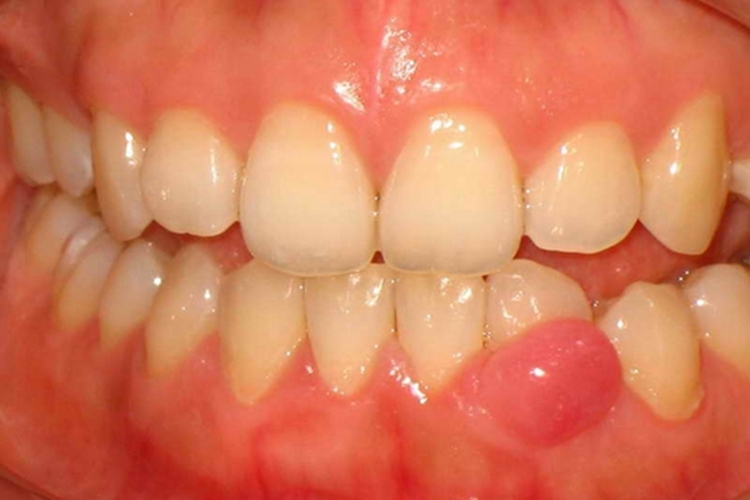

成人牙龈囊肿:成人牙龈囊肿较小,可为单囊或多囊,可表现为缓慢增大的无痛性牙龈肿块,病变界限清楚,发生于附着龈或牙间乳头内,位于唇颊侧。表面光滑,呈正常牙龈色或淡蓝色。质软,有波动感,邻牙有活力。X线检查患区骨无改变,或仅表现较为模糊的圆形密度减低影像。